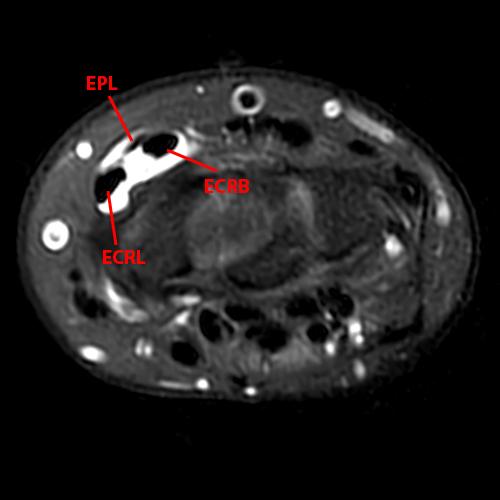

Distal Intersection Syndrome occurs where the EPL crosses dorsal to the extensor carpi radialis longus (ECRL) and extensor carpi radialis brevis (ECRB) tendons (Figure 10). Proposed mechanisms include stenosis from the overlying extensor retinaculum and intrinsic stenosing tenosynovitis. Communication is typically present between these tendon sheaths, and tenosynovitis may secondarily spread from one compartment to the other. These patients present with radial-sided dorsal wrist pain. The fluid-sensitive MRI series demonstrate the involved tendons, which may show thickening of the tendon sheaths, tenosynovitis, edema, and abnormal intrasubstance tendon signal (Figure 12).22,40,41

Figure 12: 21-year-old female with dorsal radial pain and swelling with clinical concern of de Quervain’s tenosynovitis. A fat-suppressed proton density-weighted coronal (12A) and axial (12B) images demonstrate tenosynovitis involving the tendon sheaths of the extensor carpi radialis brevis (ECRB) and extensor carpi radialis longus (ECRL) tendons and the crossing extensor pollicis longus (EPL) compatible with a distal intersection syndrome.